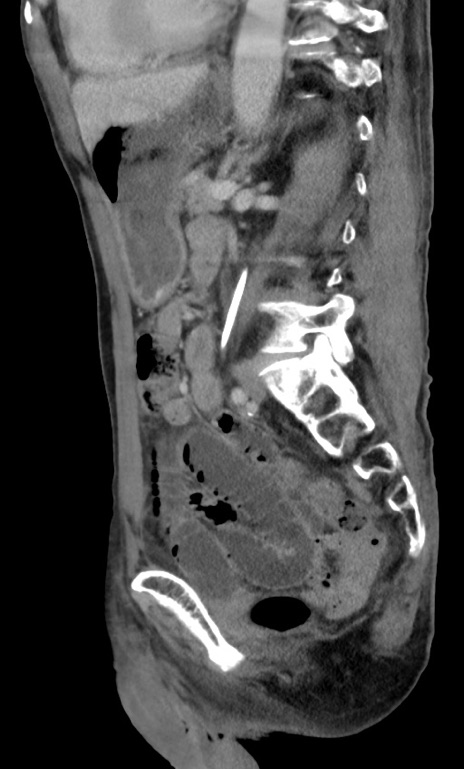

症例3(矢状断像)

【症例】 70歳代男性

【主訴】右鼠径部腫瘤、疼痛

【現病歴】本日朝より上記主訴あり、受診。

【既往歴】膀胱癌にて膀胱全摘、両側尿管皮膚瘻

【データ】WBC 5600、CRP 0.56